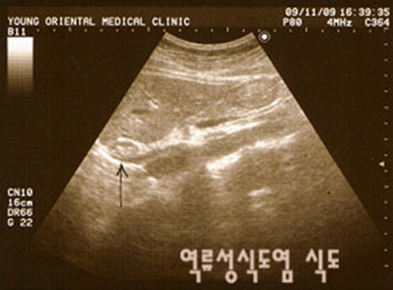

날씨가 무더워 지면서 식욕이 없고 불규칙한 식생활로 속이 쓰리는 경험을 해본 적이 있을 것 이다. 보통 위산이 넘어와 속이 쓰리다고 표현하는 위식도 역류증은 위, 십이지장의 내용물이 식도로 역류돼 증상을 일으킨다. 이중에서도 염증을 동반한 궤양 등의 식도 점막 손상이 있는 경우 역류성 식도염이라고 한다.

역류성식도염은 위나 십이지장의 내용물이 식도로 역류해 점막에 손상을 줌으로써 염증 및 궤양, 출혈 등을 일으키는 질환으로 악화되면 식도암까지 유발할 수 있다. 역류는 대부분의 사람에서 트림 등 정상적 생리현상이나 역류성식도염은 역류가 자주되거나 역류지속시간이 비정상적으로 지속돼 점막 자극과 통증을 유발한다.